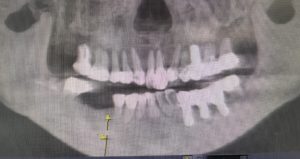

午前中のオペ

左下6番欠損に対してストローマンBLXインプラントを植立しました。

直径6.5×6mm 骨が少なくても刺さりますね。